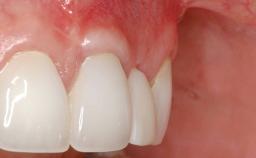

Adequate peri-implant soft-tissue thickness is essential not only for esthetic but also for functional reasons. In this case, Vincenzo Iorio Siciliano demonstrates how he achieved increased height and thickness of posterior peri-implant soft tissues to obtain a stable mucosal seal and a width of keratinized tissue favorable to toothbrushing.

The patient, a healthy 38-year-old woman, was referred for increasing the width of the keratinized tissues at the buccal aspect of dental implant 46. The site exhibited a premature-closure screw exposure caused by trauma during chewing, with inadequate keratinized tissue.